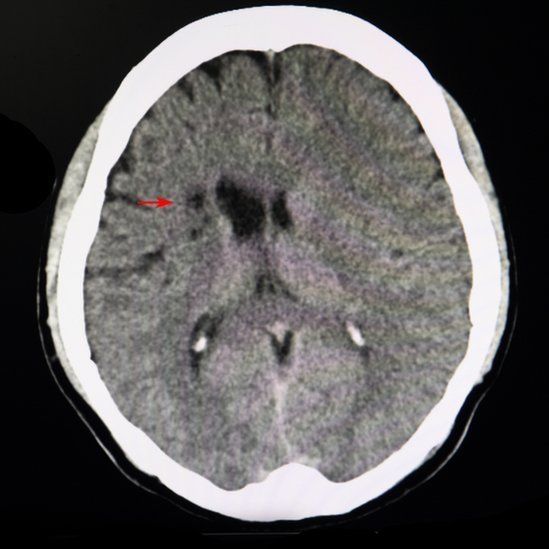

El daño es tan pequeño que no generan síntomas obvios y sólo se pueden observar con una imagen por resonancia magnética (IRM) o una tomografía computarizada (escaneo TC).

"Se ven como un pequeño puntito", indica la doctora Koppel. "Muchas veces, cuando les preguntamos, los pacientes ni se dieron cuenta de que les pasó algo".

Un infarto cerebral silencioso sólo se puede confirmar con una imagen por resonancia magnética (IRM) o una tomografía computarizada (escaneo TC)